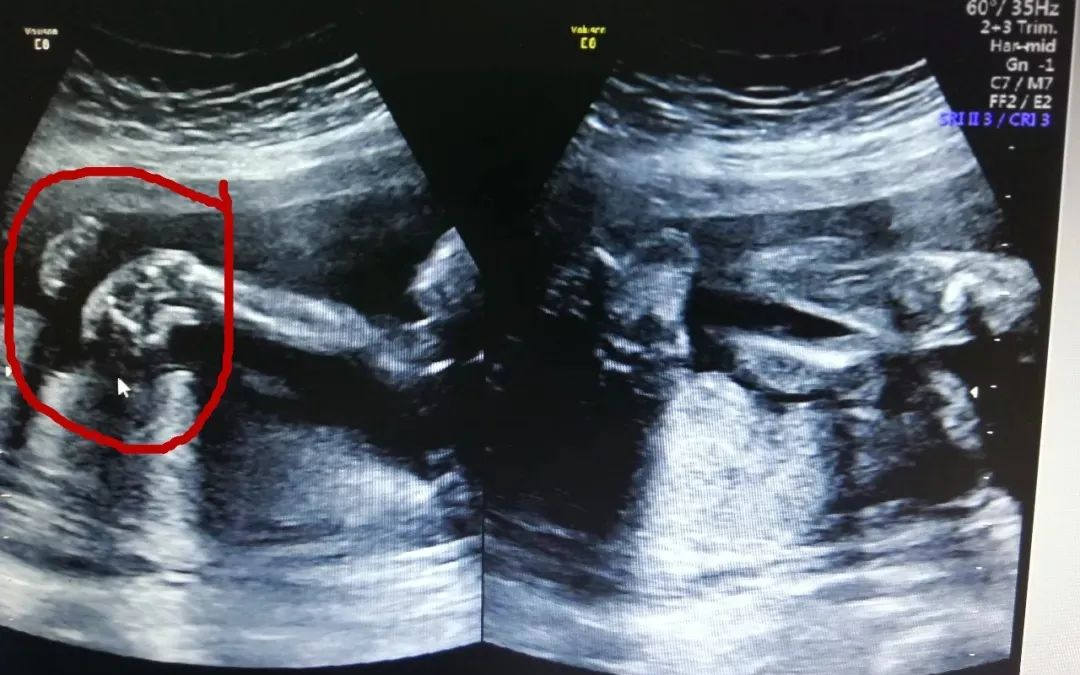

四维排畸

(通过四维彩超检查出唇裂、足内翻等畸形)